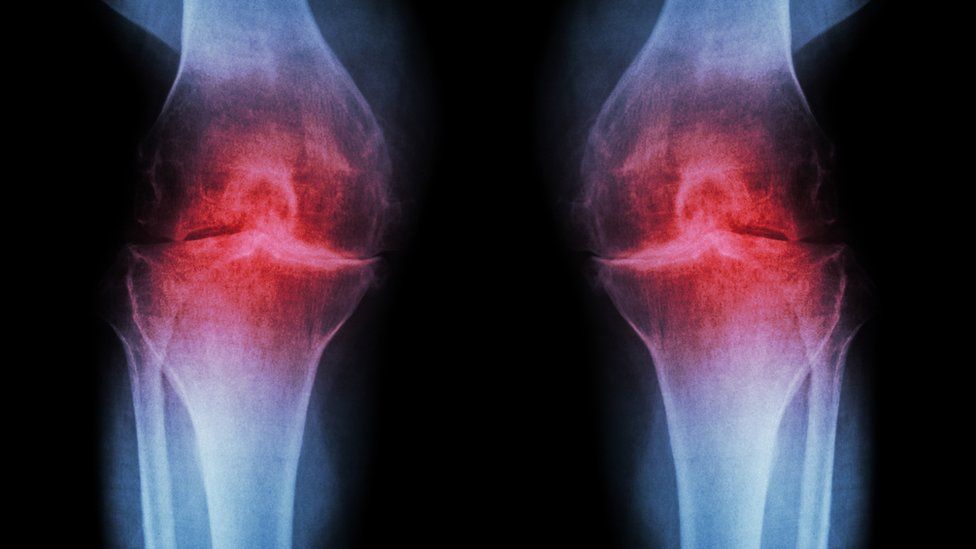

The device could be useful for minimizing arthritis pain depending upon how severe the pain is. By stimulating the acupuncture points, the pain can be lessened to some extent. When the device is used by patients with knee osteoarthritis, they may notice a reduction in inflammation and stiffness. It can help patients in increasing the mobility of the knees and may significantly improve their quality of life. Poor blood circulation can also cause pain in the legs, feet and arms. Hence, you may find the device useful for increasing blood circulation.